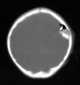

Depressed skull fracture

A skull fracture is a break in one or more of the eight bones that form the cranial portion of the skull, usually occurring as a result of blunt force trauma. If the force of the impact is excessive, the bone may fracture at or near the site of the impact and cause damage to the underlying structures within the skull such as the membranes, blood vessels, and brain. [Source: Wikipedia ]